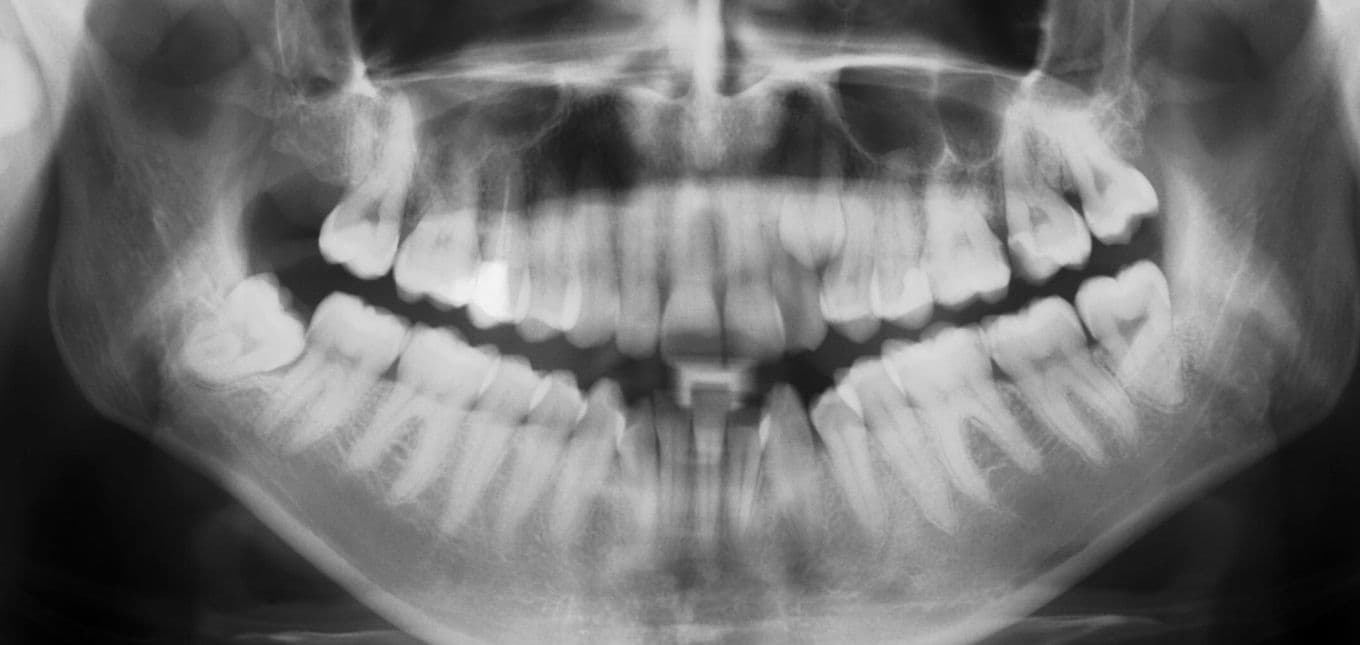

Visdomstennene sitter helt bakerst i munnen på begge sider, oppe og nede. De bryter oftest frem når du er mellom 18 og 25 år, og dette kan være ubehagelig for mange. Noen får bare en eller to visdomstenner, og det hender at de ikke kommer i det hele tatt.

Når visdomstennene har dårlig plass, kan det irritere tannkjøttet omkring og gi infeksjon. På grunn av visdomstennenes plassering kan det også bli vanskelig å rengjøre dem skikkelig, slik at det oppstår tannråte. Som en følge av menneskets evolusjon har nemlig kjevene våre blitt mindre, og det er derfor ofte ikke plass til visdomstenner. Det blir trangt og vanskelig å komme til med tannbørste og tanntråd.